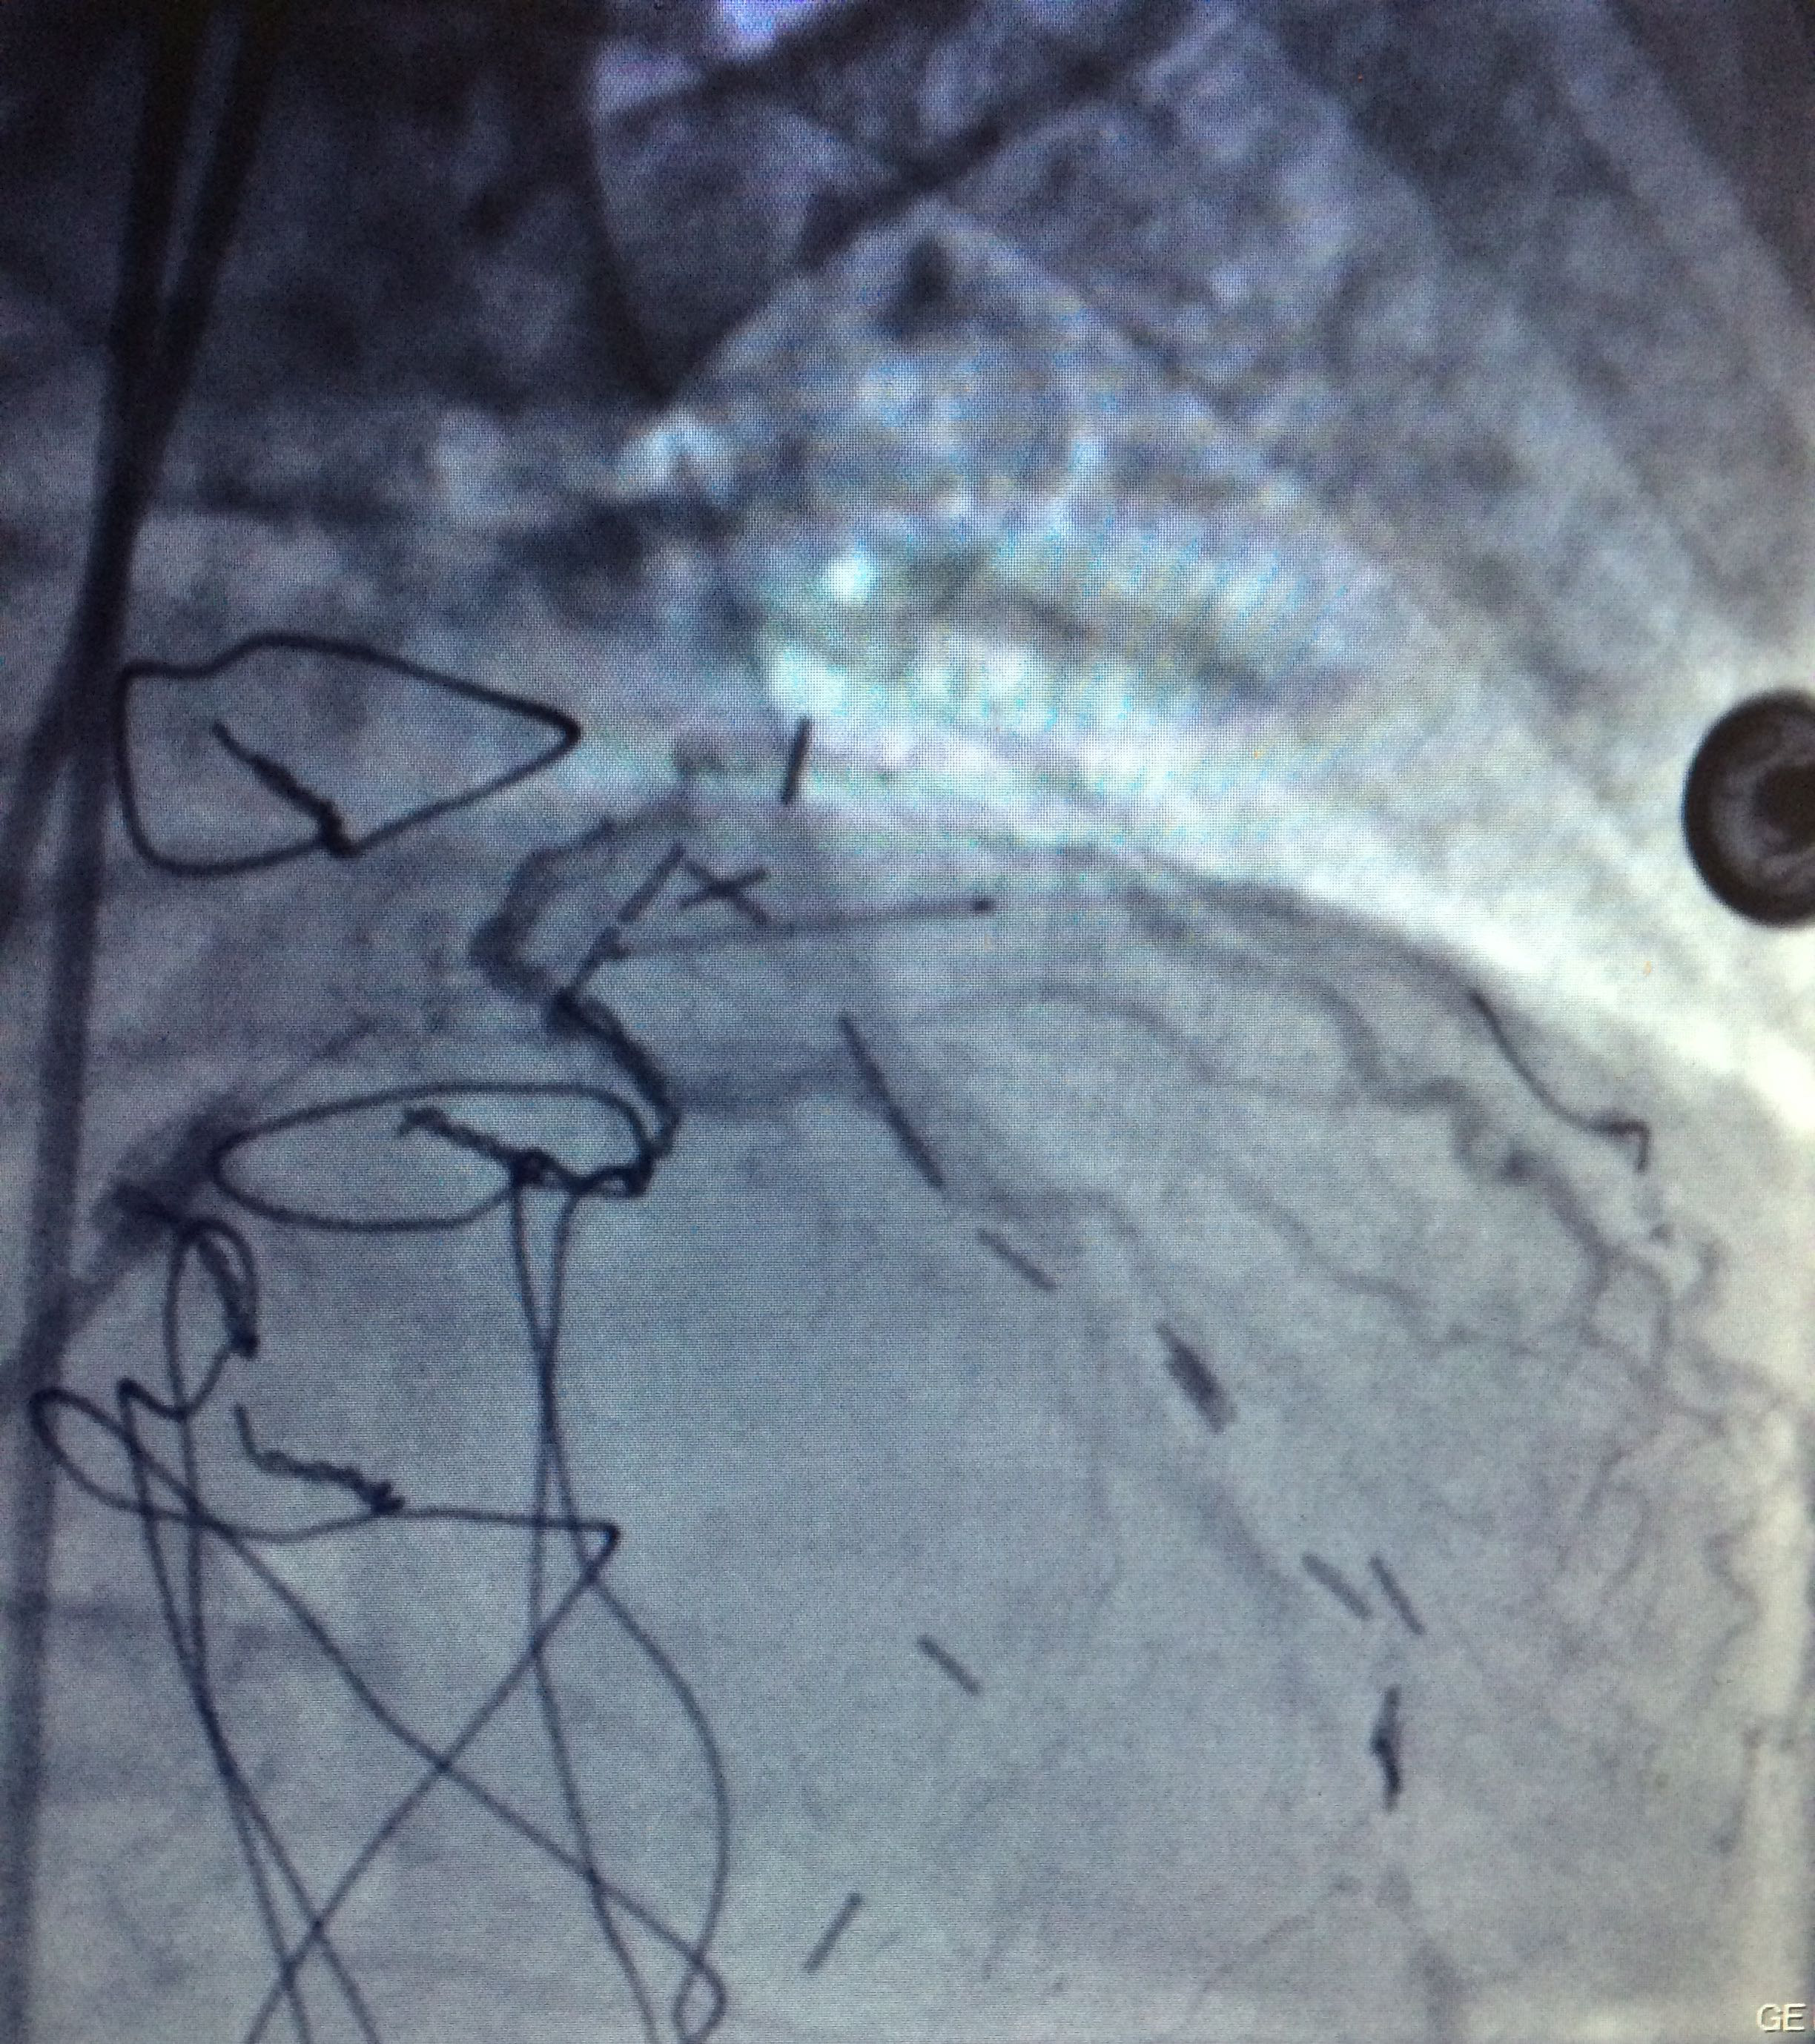

Figure 2 Right coronary artery with total occlusion at the proximal third.

Figure 3 Through a conventional right femoral approach, the left coronary ostium was canalized using a 4.0 6Fr Launcher guiding catheter (Medtronic). Subsequently, a floppy microguide at the level of the anterior left descending artery was used to cross the lesion. Balloon dilation was performed to open the vessel starting with a 1.5x18mm Sprinter balloon (Medtronic) followed by a 2.0x22mm to finally deploy a 2.5x18mm Endeavor stent at 18atm for 10 seconds at the level of left anterior descending artery obtaining a satisfactory angiographic result.

Procedure

Through a conventional right femoral approach, the left coronary ostium was canalized using a 4.0 6Fr Launcher guiding catheter (Medtronic). Subsequently, a floppy micro guide at the level of the anterior left descending artery was used to cross the lesion. Balloon dilation was performed to open the vessel starting with a 1.5x18mm Sprinter balloon (Medtronic) followed by a 2.0x22mm to finally deploy a 2.5x18mm Endeavorstent at 18 atm for 10seconds at the level of left anterior descending artery obtaining a satisfactory angiographic result (Figure 3-6).